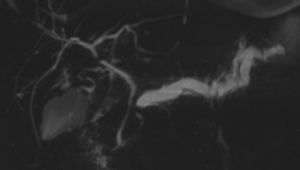

image

Lesione non visibile all’imaging. All’esame RM dilatato il dotto pancreatico principale con stop in regione istmica in assenza di visualizzazione di lesioni focali nelle sequenze precontrastografiche.